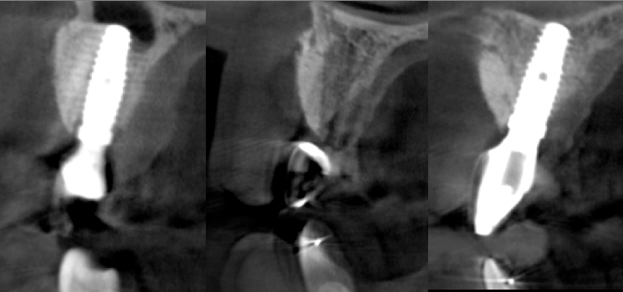

After the 3rd bone graft failed, the patient sought second opinions. She was a college sophomore at the time. Using a combination of interdisciplinary therapies, including S.M.A.R.T. minimally invasive bone grafting, Dr. Ernesto Lee was able to tridimensionally reconstruct this severe defect and place implants to restore the patient’s smile. The S.M.A.R.T. bone graft was also extended to treat adjacent teeth with thin/dehisced bone.

A long-term CAD/CAM fabricated temporary restoration is in place while she finishes medical school at an out-of-state university. The treatment of this case was published in detail in a special issue of the Compendium of Continuing Education in Dentistry, one of the largest circulation journals in our profession.